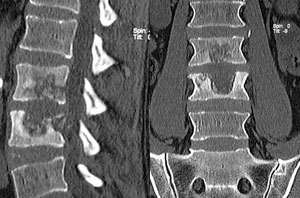

Casos Complejos 2

Cifosis rigida toracolumbar (Enfermedad de Scheuermann): varón de 20 anos, consulta por dolor toraco lumbar intenso, realizo 4 anos de terapia física y rehabilitación sin éxito.

10 meses Post-operado, se tuvo que realizar varias osteotomías de columna, actualmente sin dolor, realiza actividades cotidianas sin limitaciones.